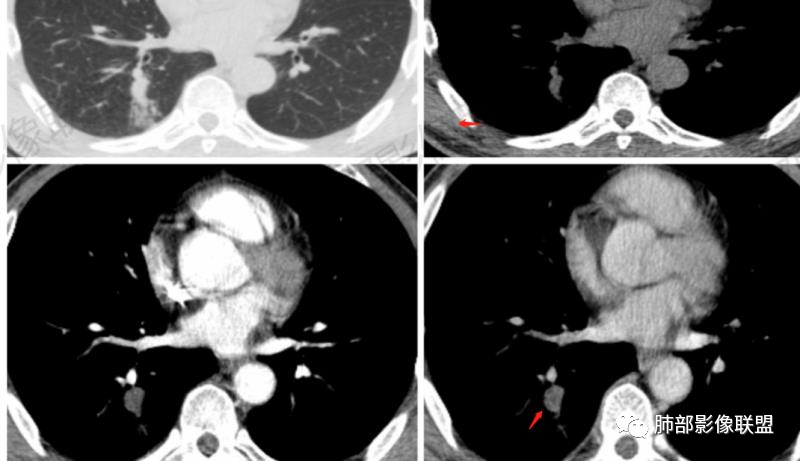

2.右肺下叶背段指尖大小结节影伴外围片状影及小结节影,片影中有结节感。

3.近背段支气管开口附近结节密度不甚均匀,未见钙化或脂质密度区。边界清楚光整,内侧平直,未见典型深分叶及毛刺,增强扫描轻度强化。

5.背段支气管于结节内侧份“旁现侧出”,管壁完整,管腔少量分泌物,近乎疏通状态。结节内隐约出现微小含气空腔。

1.会是肺腺癌吗?较长时间段内固定存在的结节影我们会想到新生物。本例结节影边界清楚光整,内缘平直,缺乏典型深分叶及毛刺,未见异常强化,未见肿大淋巴结等,缺乏肺腺癌的依据。

2.会是硬化性肺细胞瘤吗?病灶支气管相关,未见异常强化,短期内增大等几乎完全将硬化性肺细胞瘤排除在外。

3.同样的理由也不支持错构瘤,尽管结节影密度不均匀。我们几乎不可能在错构瘤中观察到如此穿行的支气管!

4.会是隐球菌感染吗?急性感染,如易形成空洞的肺炎克雷伯杆菌感染等我们自然不在考虑之列,无论是临床表现还是影像学改变。肺部隐球菌病灶有时酷似新生物,但如此漫长不出新花样的侵袭性病灶则非常罕见!

5.临床表现轻微的病灶还有肺结核!可以长期“默默无闻”。本例结节影密度欠均匀,强化不显著,可以出现小空洞,周围见小结节影等,结核确实存在众多支持点。

不事张扬的小空洞,最常见的还是结核!

6.外围片影的迅速扩大应考虑为继发性改变,不宜单以结核感染本身加以解释。